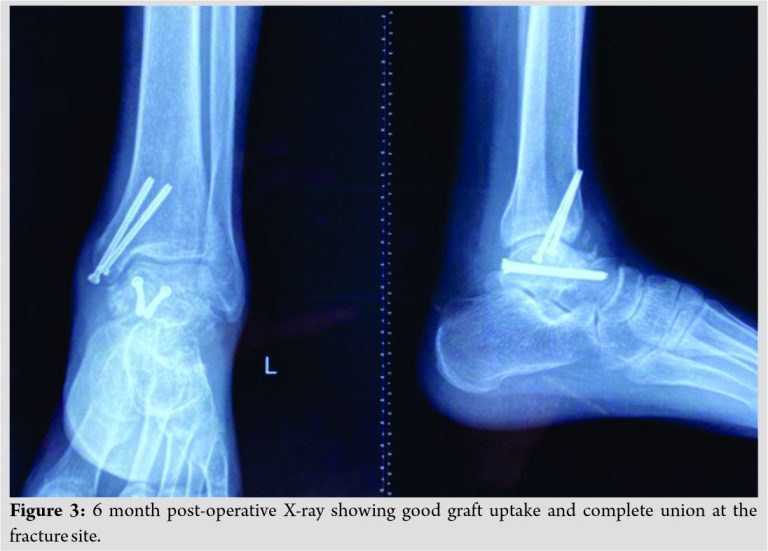

The patient was advised non weight bearing mobilization for 4 weeks. Partial weight bearing mobilization started at 5 weeks postoperatively, while full weight bearing mobilization was not done until 3 months postoperatively. Serial radiographs were procured at 3rd and 6th month postoperatively (Fig. 2, 3). The 6th month post-operative radiograph of the patient showed features of complete union of the fracture. Clinically, the patient had no symptoms with full ankle range of movements.

Fixation of Talus neck fractures is an absolute necessity to decrease the overall risk of osteonecrosis. Vallier et al. noted that, any delay in fixation of talus neck fracture following a satisfactory reduction had no impact on the development of osteonecrosis [9]. Talus neck fractures are associated with high rates of complications, even when they are intervened timely and in the long run they eventually lead to chronic pain and stiffness off the ankle joint [10]. The disrupted blood supply leads to destruction of the organic component of the bone. The talus being the weight bearing bone develops multiple microfractures ultimately leading to collapse of the talus [11]. It is noted that the amount of soft-tissue injury and the extent of fracture displacement have direct correlation with the development of osteonecrosis [12]. The patient in the case was misdiagnosed initially. The patient presented with swelling and an un-displaced fractures on the radiograph, indicating minimal soft-tissue component, despite that the patient developed osteonecrosis. With the advent of improved surgical techniques and advanced fixation methods, it is extremely important to diagnose such cases at the earliest and a timely intervention is critical in preventing further complications. The treatment options for managing talar osteonecrosis varies from one case to another. The various treatment options available are core decompression, bone grafting, arthrodesis, partial or total talar replacement, and in extreme scenarios total ankle replacement. The choice of the procedure depends on the staging of the disease as classified by Berndt and Harty and the extent of necrosis [13]. The bone graft can be vascularized or non-vascularized (free medial femoral condyle or iliac crest graft). In our case, non-vascular iliac crest cancellous graft was used which showed an excellent outcome with complete union at the end of 6 months without any residual clinical symptoms.